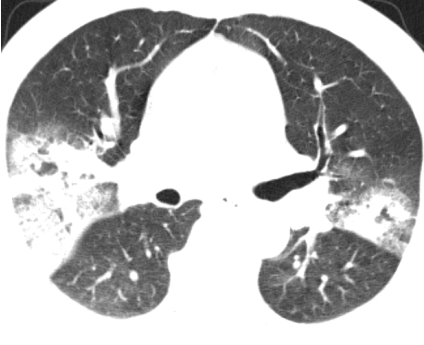

入住肺病科(呼吸内科)后,医生为患者完善了胸部CT及相关检查。影像结果显示:“双肺见片状密度增高影及实变影,边界模糊,提示双肺感染。”针对患者病情,科室立即组织了病例讨论。专家们凭借着深厚的医学知识和丰富的临床经验,深入分析病情,制定出了科学合理的诊疗方案,一天内完成了相关检查。

治疗前CT影像▲